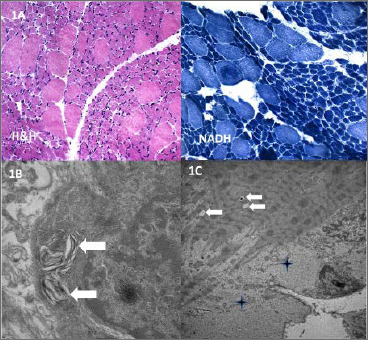

At age four, she underwent neurological evaluation. Serum creatine kinase levels were within normal range. Electromyography revealed a myopathic pattern. Cardiological and cognitive assessments were unremarkable. A muscle biopsy showed type 1 fiber atrophy relative to type 2 fibers, consistent with fiber-type disproportion (Fig. 1A).

Ultrastructural analysis of a muscle biopsy confirmed fiber size variability with both small and atrophic fibers. Many fibers contained myelinoid-like elements composed of membranous structures, predominantly located in the subsarcolemmal region, possibly derived from the sarcotubular system. Some intermyofibrillar vacuoles and rare accumulations of nonspecific granulofilamentous material were also observed (Fig. 1B-C).

Figure 1. (A). Muscle biopsy. H&E and NADH staining show numerous hypotrophic type 1 fibers (dark blue on NADH) surrounding hypertrophic or normal type 2 fibers (light blue on NADH), suggestive of a fiber-type disproportion myopathy. No central nuclei, cores, fiber degeneration, or increased endomysial connective tissue were observed. (B-C). Ultrastructural analysis. Myelinoid-like elements composed of membranous structures are visible in the subsarcolemmal region (white arrows) (B). A few vacuoles are present in the intermyofibrillar space (white arrows), along with nonspecific granulofilamentous material in the subsarcolemmal region (crosses) (C).